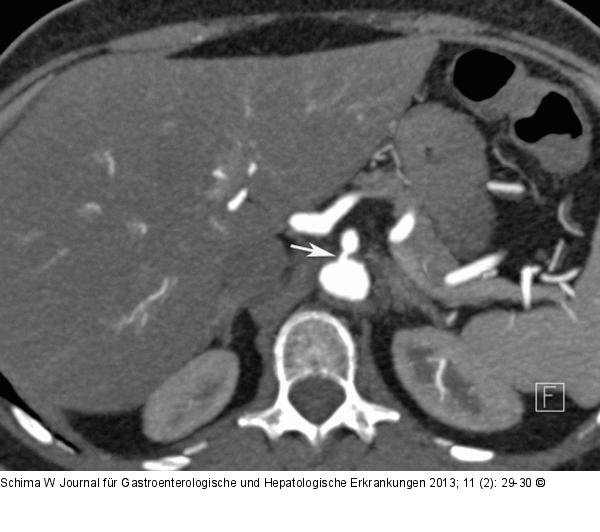

Abbildung 1a: MDCT-Angiographie Die MDCT-Angiographie in axialer Schichtführung zeigte eine kurzstreckige, hochgradige exzentrische Abgangsstenose de A. mes. sup. (Pfeil). |

Die MDCT-Angiographie in axialer Schichtführung zeigte eine kurzstreckige, hochgradige exzentrische Abgangsstenose de A. mes. sup. (Pfeil). |